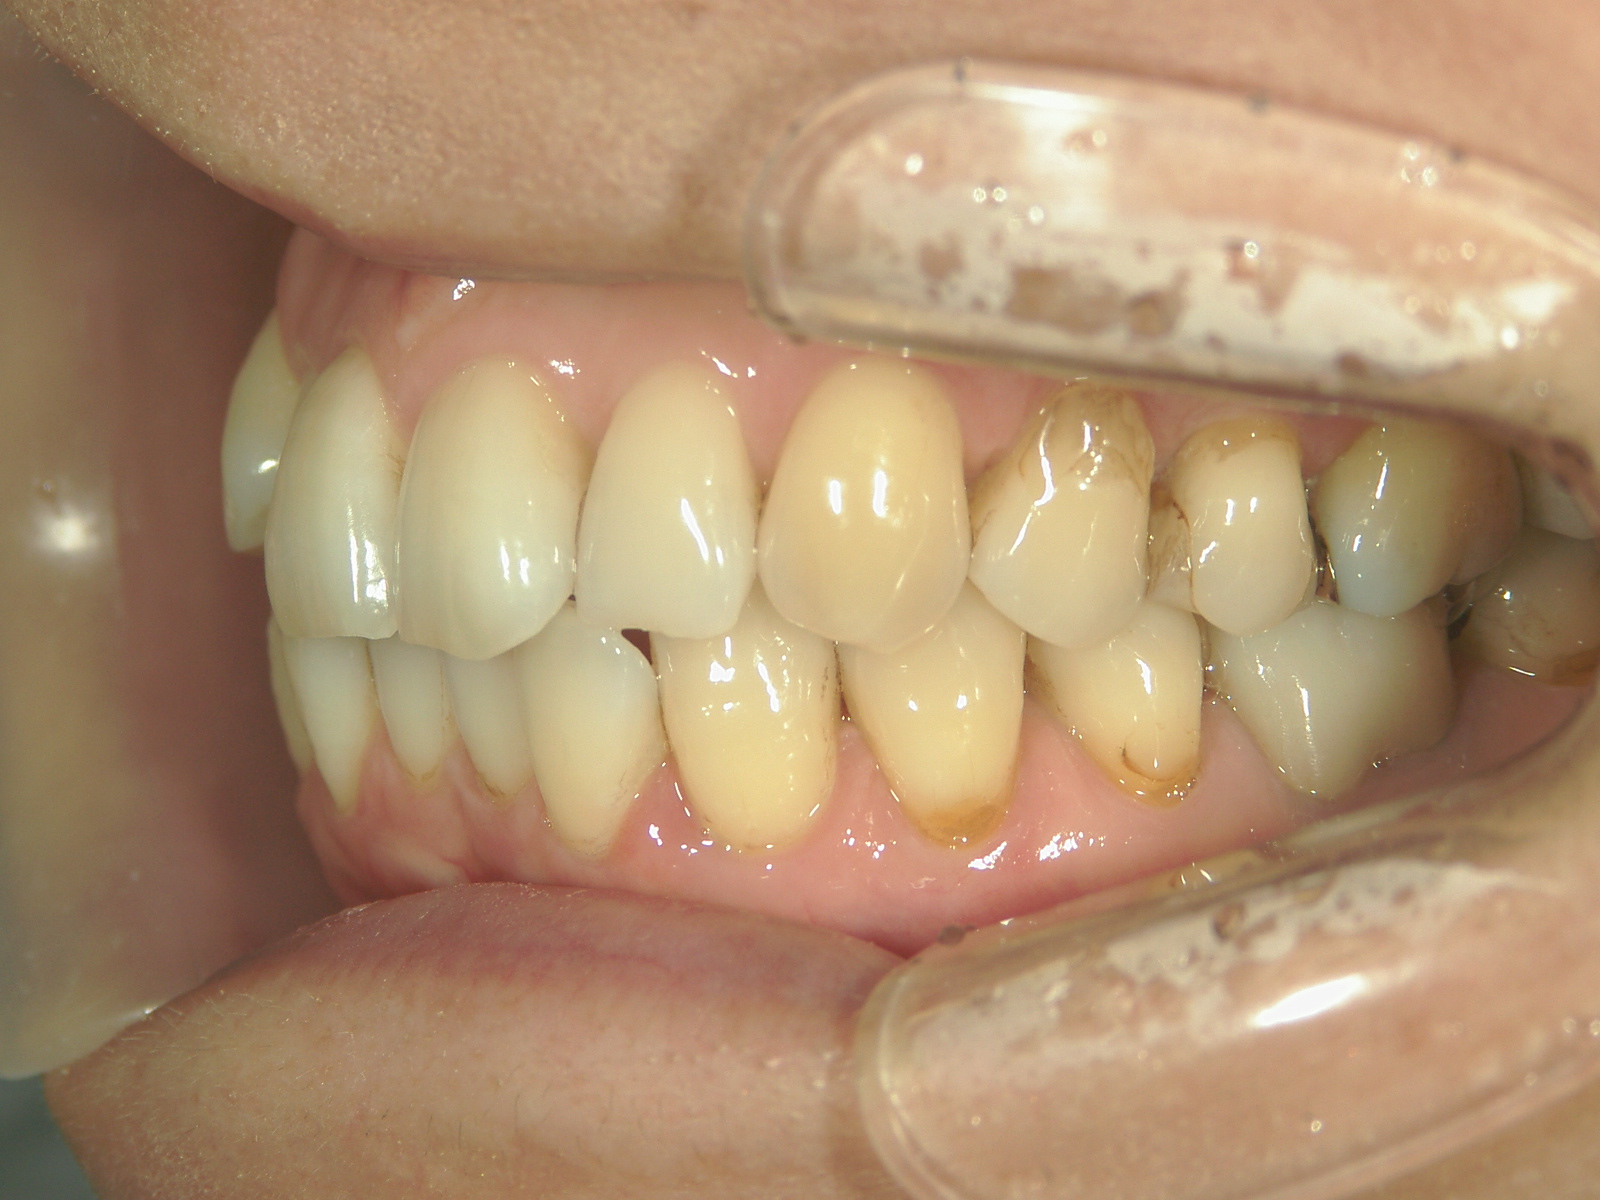

インビザライン矯正 症例(25)

主訴: ㊤前歯が出ていて、噛み合わせが気になる。

カテゴリー : ガタガタ(叢生)